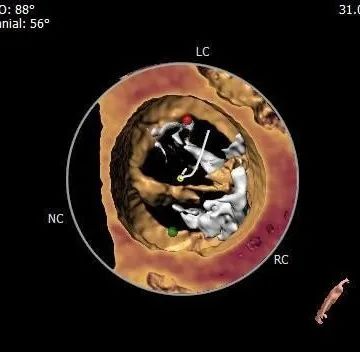

钙化分布:

左冠脉阻塞风险低